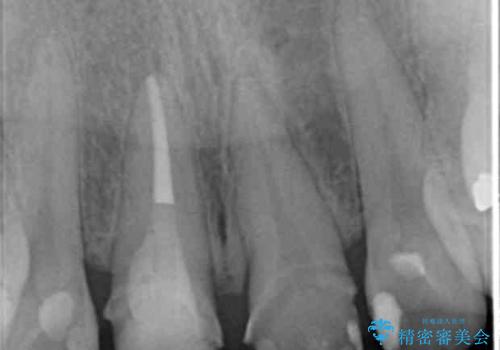

- 「 以前神経を取った歯の変色が気になる。前歯をきれいにして欲しい。」と治療を希望され来院されました。

目立つ上顎前歯に変色・大きな虫歯治療痕が見られ、審美障害を引き起こしています。

虫歯の徹底的な除去、根管治療を行いセラミック治療に入る前の環境をしっかりと整えたのち審美的なジルコニアセラミックで治療を仕上げました。